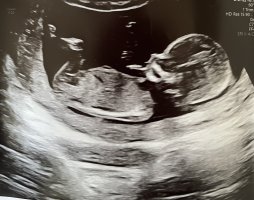

Åå nommin! Gratulere! Det der må jo være jente! NUBen er rett fremVår lille, 13 + 0!

Nub gruppen på Facebook sier jente. Jeg klarer ikke tro på det. Legen som tok TUL ble sur og ville ikke si noe om kjønn..

Vurderer nesten en privat ultralyd bare for å bekrefte/avkrefte kjønn, men må da reise mange timer, er SÅ nysgjerrigÅå nommin! Gratulere! Det der må jo være jente! NUBen er rett frem![]()